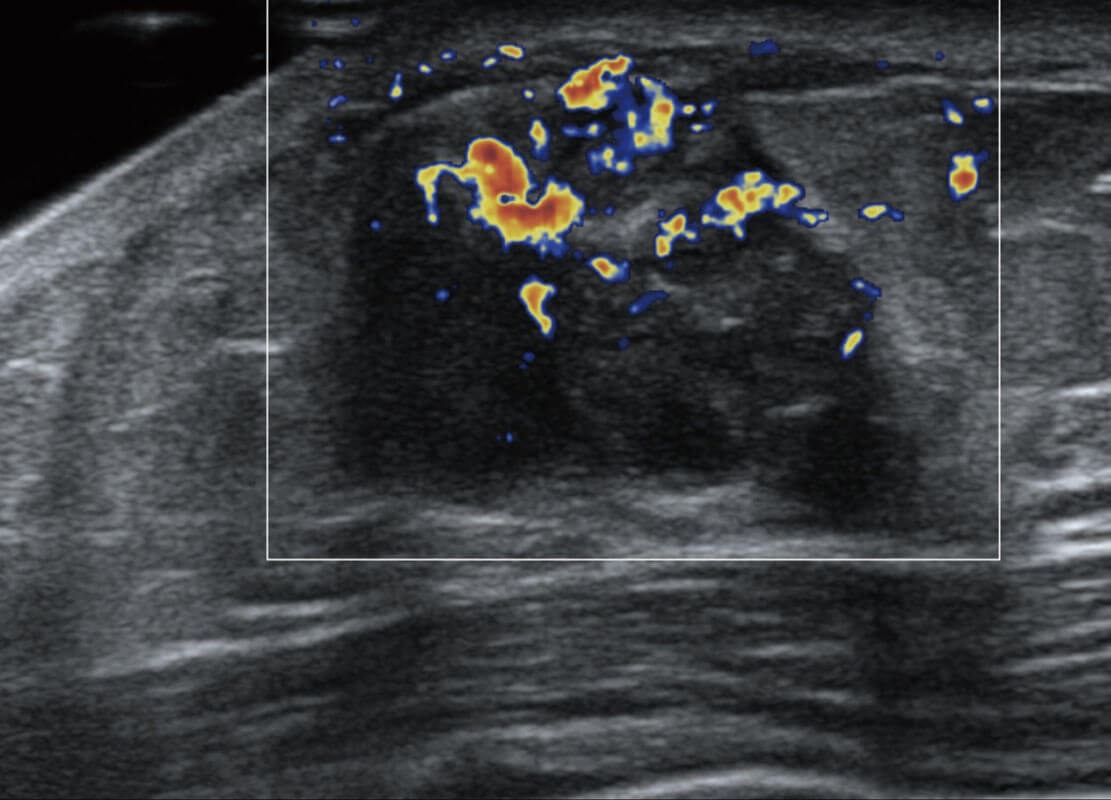

P60搭載寬頻帶線陣探頭、寬景成像、彈性成像技術(shù),為您提供乳腺應(yīng)用方案。P60支持高頻相控陣探頭、線陣探頭、腹部高頻探頭、腹部微凸探頭等,豐富的探頭群搭載敏感的彩色血流成像,適用于新生兒多種臟器檢測(cè)要求,滿足新生兒篩查需求。

乳腺癌顯微血流